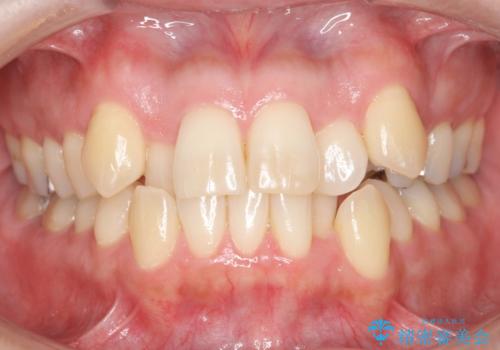

下の八重歯 歯を抜かずに インビザライン治療

- 歯並びのがたつきを主訴に来院。

抜歯してワイヤー矯正という選択肢も提案しましたが、マウスピース矯正で、歯を抜かずに並べてほしいとのことでした。

スペースを確保するために、歯をわずかに削る処置、奥歯を後ろに下げる処置(インプラント矯正)を行っています。

途中患者様のご都合で治療を中断していたため、長くかかっていますが、実質2年程度で終わる内容でした。